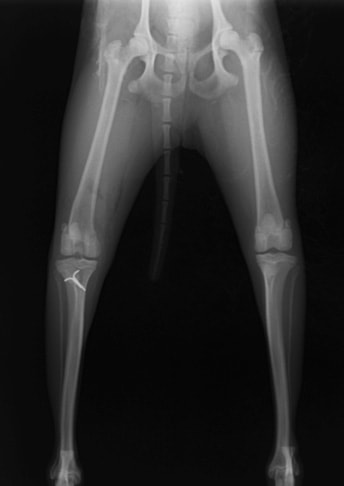

■ 症例20 ポメラニアン 8ヶ月 1.8kg

左右膝蓋骨脱臼 グレードⅢ

2ヶ月前から間欠的跛行が認められ、両膝の膝蓋骨脱臼整復術を行った。

手技は縫工筋及び内側広筋の解放、脛骨粗面の外側転位、滑車ブロック形造溝術、内外側関節包の縫縮を選択し実施した。

右側の膝蓋骨脱臼は上記手技で整復されたものの、左側はそれのみでは膝蓋骨が浮く様子が認められた。その為、PDS縫合糸にて膝蓋靱帯を1糸のみ縫合し、靱帯の縫縮を行った。

膝蓋骨脱臼は膝関節における膝蓋骨の内外側の脱臼と定義されるが、時として単純な内外の脱臼ではなく、膝蓋骨が大きく前方に浮き上がるように脱臼する場合がある。特にトイプードルやポメラニアンといった犬種に多く認められる。

内側脱臼に加えて前方への浮き上がりを矯正する為に、従来より脛骨粗面転移により膝蓋靭帯を外方と下方に引っ張り、固定する方法を選択する。膝蓋骨の前方への浮き上がりが軽度の場合は、従来法ではなく関節包の縫縮で対応していた。しかし、一部の症例で膝蓋骨の動きが悪くなり伸展機構が円滑に機能せずロボット様歩行になるケースがあった。

その為、膝蓋靭帯自体を縫縮する方法を採用した。この方法により、膝関節の伸展機構を妨げず膝蓋骨の軽度の浮きを矯正することが可能となった。

本症例の経過は良好である